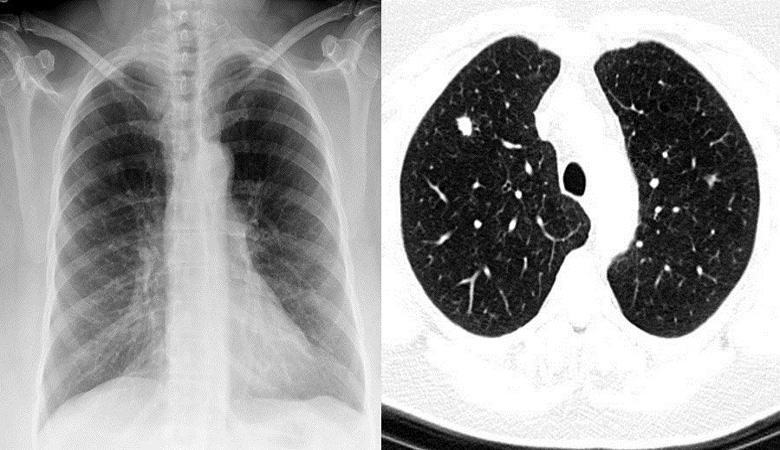

U 2016. godini očekuje se umirovljeni Joe Tippens iz Oklahome tragične vijesti: ljekari su mu dijagnosticirali karcinom malih ćelija pluća u posljednjoj fazi. Početkom 2017. metastaze proširila se po gotovo cijelom Amerikancu. Osiguravajuće društvo potrošio je više od 1,2 miliona dolara za liječenje muškarca, ali bez uspeha. Kao rezultat toga, ljekari su našem heroju dali ne više od tri meseci života. Ali tada se, prema Tippensu, nešto dogodilo zaista neverovatno.

Onkologija